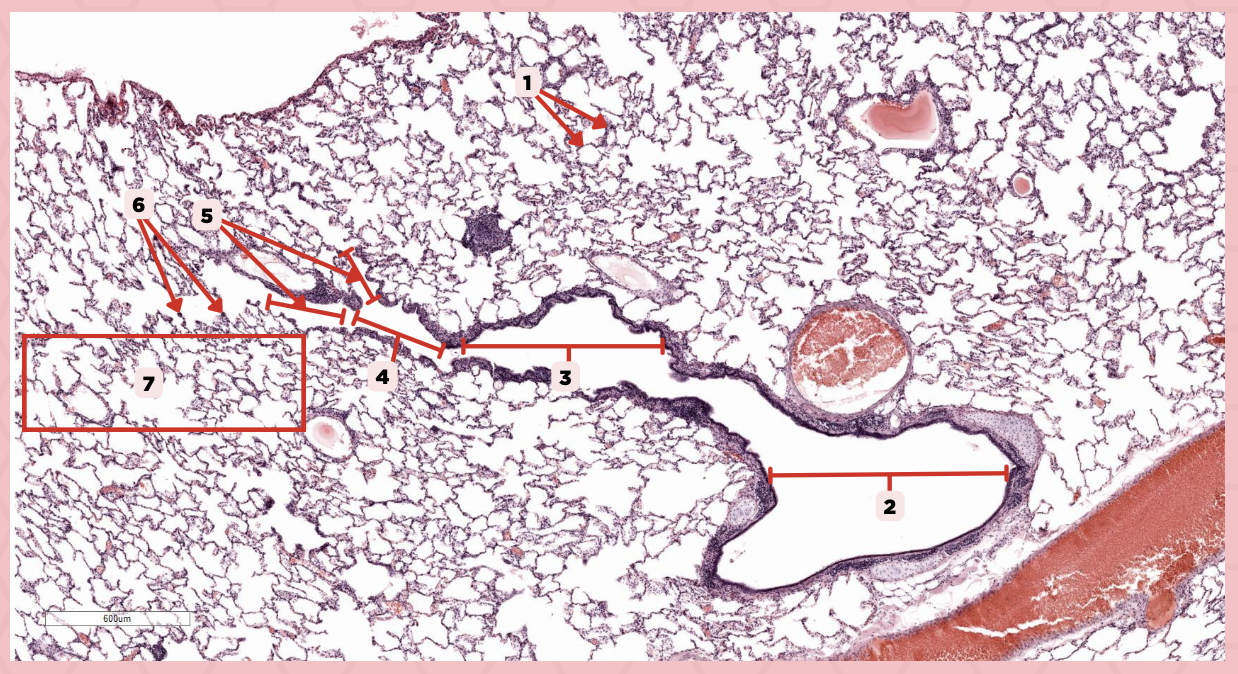

Interalveolar septa

Identify the structure labeled as 1.

Intrapulmonary bronchi

Identify the structure labeled as 2.

Bronchiole

Identify the structure labeled as 3.

Terminal bronchiole

Identify the structure labeled as 4.

Respiratory bronchiole

Identify the structure labeled as 5.

Alveolar ducts

Identify the structure labeled as 6.

Alveolar sacs

Identify the structure labeled as 7.

Bigger and smaller intrapulmonary bronchi

What are the two types of intrapulmonary bronchi?

Pseudostratified epithelium (bigger bronchioles), Simple columnar or cuboidal (smaller)

What are the types of epithelium in No. 3?

Deoxygenated blood

What type of blood does vessel No. 1 carry?

Connective tissue septae

Where would No. 2 be located?

Pulmonary artery

Identify the structure labeled as 1.

Tributary of pulmonary vein

Identify the structure labeled as 2.

Oxygenated blood

What type of blood does this vessel supply?